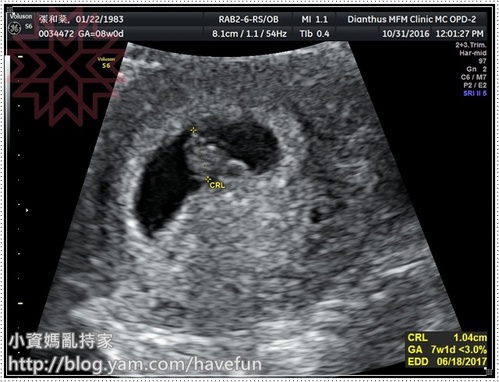

沒想到10周多的產檢,她安安穩穩的待在肚子裡,還不斷的對著我揮手扭腰

因為滿三個月,禾馨機器很清楚,應該可以看到性別(想當初老大在三總可是6個月才看到鳥阿)

因為一進門我們就在聊看不看的到性別,陳醫師一坐下來,就特別先幫我照寶寶的屁股,

還說"你先告訴我你想要男生女生", 我回答後,才告訴我答案

之後也很細心的幫我照了寶寶的手腳,還數了五根指頭,也看了腦部,耳朵鼻子

不得不說,禾馨的機器真的超級清楚啊!我之前在三總三個月的超音波根本只是一團白霧嘛!

自費項目才會檢查的子宮動脈血流(檢查子癲前症),陳醫師也特別幫我做了